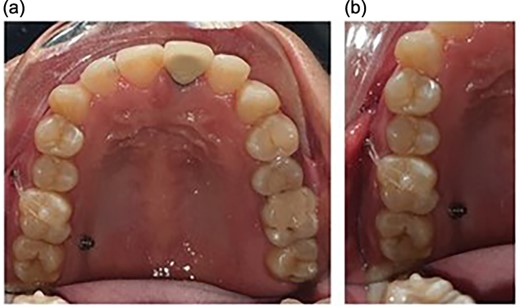

Allowed for placement of full coverage crown on the implant placed to replace the mandibular first molar (Fig. 4).

Full coverage crown placed on the implant to replace the mandibular first molar.